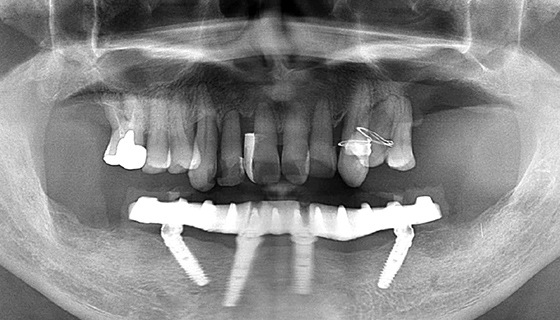

治療前

この症例では下顎の歯周病が特に進行していて、歯がクラグラで噛みにくい為、下の歯を抜歯してオールオン4で治療、上は特に歯周病が進行している左側の大臼歯を抜歯して経過観察することにしました。